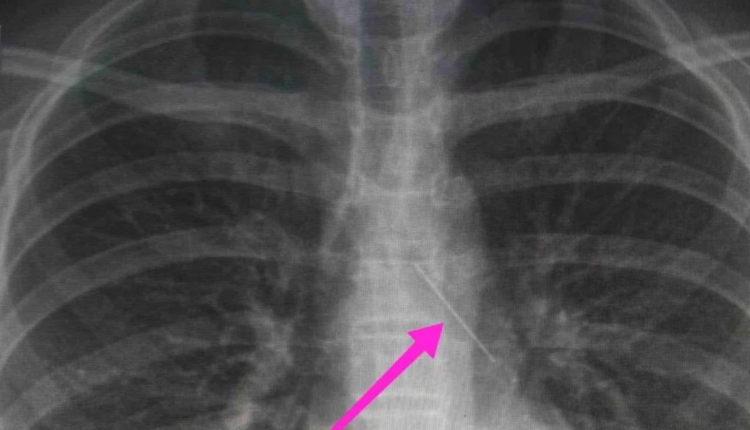

Κατά την βρογχοσκόπηση διαπιστώθηκε η μετακίνηση και ενσφήνωση του ξένου σώματος στον δεξιό κύριο βρόγχο. Μετά από εργώδεις προσπάθειες ολοκληρώθηκε με επιτυχία η αφαίρεση αυτού. Η ασθενής ανένηψε πλήρως εντός της χειρουργικής αίθουσας. Η ασθενής μεταφέρθηκε για παρακολούθηση και νοσηλεία στη Γ’ Παιδιατρική Κλινική.

Η ανήλικη ασθενής μεταφέρθηκε για παρακολούθηση και νοσηλεία στη Γ’ Παιδιατρική Κλινική.